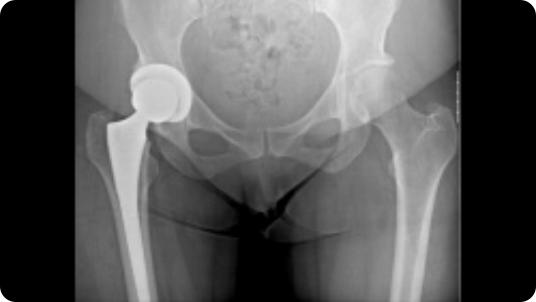

Radiographic image of hip arthritis Radiographic image of a total hip replacement

Hip Arthritis

Total Hip Replacement